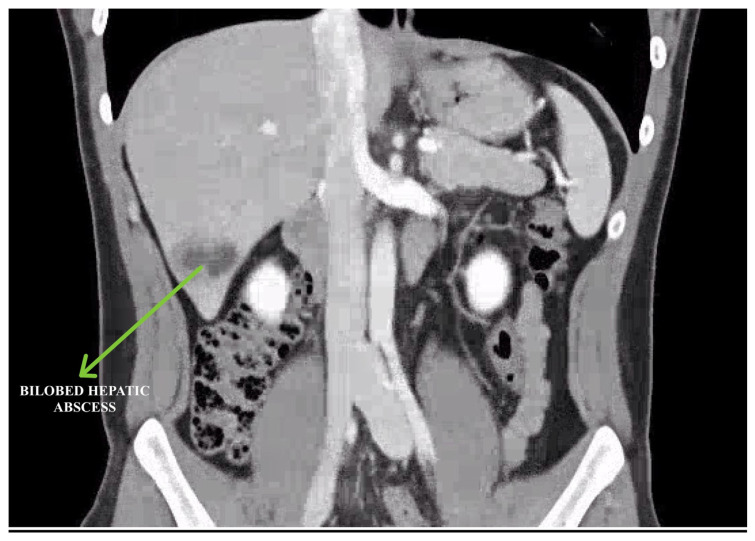

A 'Fluke' Diagnosis: Suspecting Fascioliasis as a Rare Cause of Hepatic Abscess.

Hepatic abscess is a rare complication of fascioliasis, with fewer than 50 reported cases worldwide. The diagnosis requires a high degree of suspicion and is often identified after extensive investigation leading to delays in treatment. With this case report, we aim to highlight the need for a higher index of suspicion in non endemic regions like the USA, especially in cities with large immigrant populations. Given the ease and success rates of treatment with oral triclabendazole, the morbidity from unnecessary invasive testing and disease burden is preventable with a thorough evaluation and targeted clinical assessment.